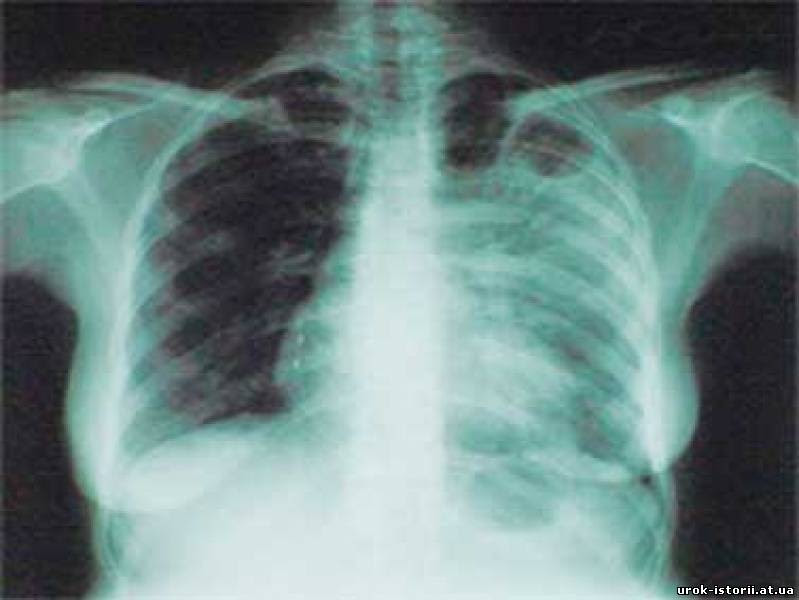

Це - небезпечна хвороба, дуже легко передається крапельним шлягом від хворої людини до здорової. Високий темп життя, нерегулярне та збалансоване харчування, стресові ситуації приводять до різкого зниження захисних сил організму, що приводить до появи захворювання і його прогресування. Хвороба може проявлятися без кліничних симптомів і начальні стадії його можна виявити тільки при вчасному звернені до лікаря та при проходженні флюорографічного обстеження.

На Закарпатті вже не перший рік, як розгорнута робота по ранньому виявленню туберкульозу. З цією метою лікувальною мережею проводяться масові профілактичні огляди населення і флюорографія. Флюорографічне обстеження абсолютно нешкідливе для організму. Його повинні пройти усі без винятку один раз у два роки. Обов’язковому обстеженню раз на рік підлягають працівники шкіл, профтехучилищ, дитячих дошкільних та інших навчальних закладів, тваринницьких ферм і птахоферм, торгівлі, медики. Діти і дорослі, які проживають з туберкульозними хворими, повинні систематично перевіряти своє здоров’я у протитуберкульозному диспансері.

Масові профілактичні огляди населення і флюорографія допомагають своєчасно виявити хворих на туберкульоз і забезпечити їх лікування. Тож, обов’язково відвідайте кабінет флюорографії - без запису і черги!